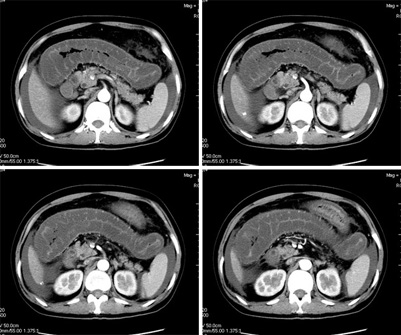

这个病例有脱发的病史,后转到风湿科,确诊为sle,经过一段时间的激素治疗,病情好转,以下是今日复查的ct

系统性红斑狼疮(sle)是一种累及多系统多器官,临床表现复杂,病程迁延反复的自身免疫性疾病。 sle的临床表现无固定模式,病程迁延,反复发作,间有长短不等的缓解期,起病可为暴发性、急性或隐匿性。

其中,消化系统症状:可出现恶心、呕吐、腹痛、腹膜炎、肠系膜血管炎、肝酶增高等。

糖皮质激素治疗,能抑制炎症细胞聚集,具有抗增殖和免疫抑制作用,是最强力的抗炎剂,是治疗sle的最主要药物,是sle的基本疗法。